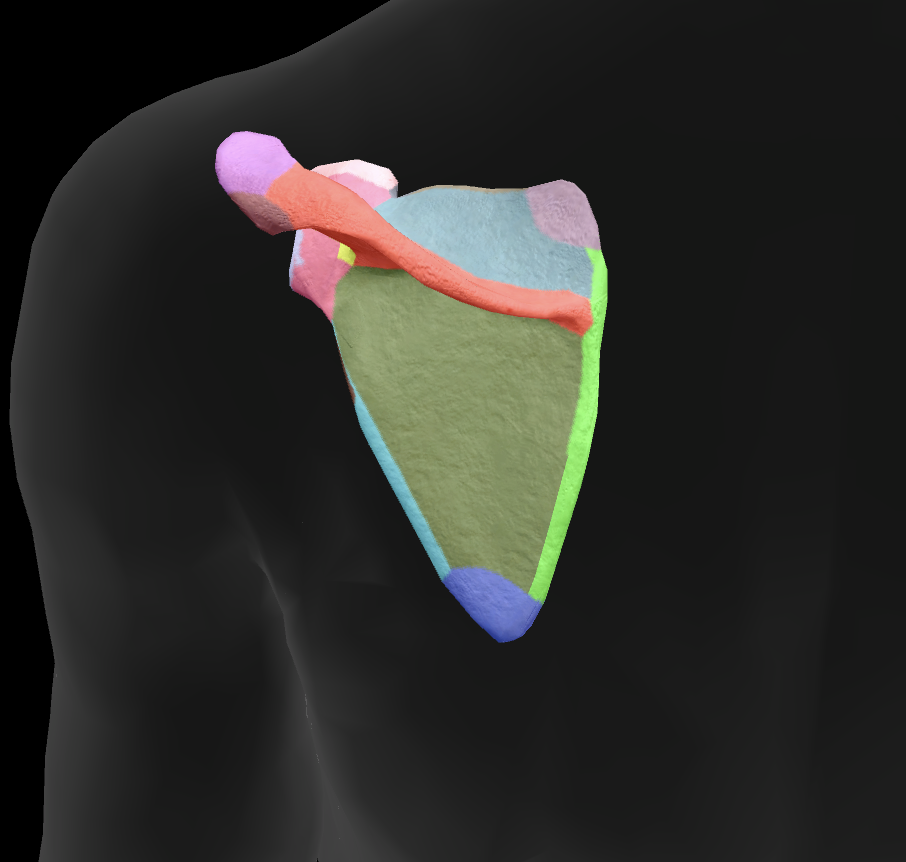

What bone is this?

scapula

What is this boney landmark?

spine of scapula

What is this boney landmark?

supraspinous fossa

What is this boney landmark?

infraspinous fossa

What is this boney landmark?

acromion process

What is this boney landmark?

superior angle

What is this boney landmark?

inferior angle

What is this boney landmark?

lateral border

What is this boney landmark?

medial border

What is this boney landmark?

subscapular fossa

What is this boney landmark?

spinoglenoid notch

What is this boney landmark?

glenoid fossa

What is this boney landmark?

supraglenoid tubercle

What is this boney landmark?

infraglenoid tubercle

What is this boney landmark?

coracoid process